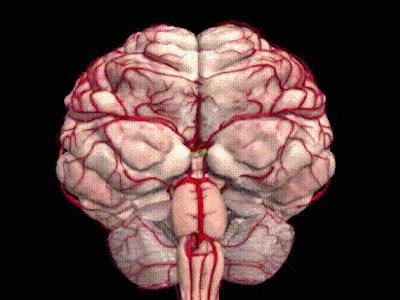

脑干出血3D示意图

恶化几率: 脑海绵状血管瘤一般无良恶性之分,但当其生长在脑干、丘脑、基底节、延髓等部位会极其危险,随时可能出现出血。以脑干出血为例,出血量少于3ml死亡率70%,5ml以上死亡率90%左右,而超过10ml则死亡率达到100%,未出过血的脑海绵状血管瘤年出血率为0.6%,但是出过一次血的脑海绵状血管瘤年出血率高达4.5%~22. 9%,反复出血的患者年出血率更高,所以患者尤其需要警惕。

治疗策略:手术切除病灶是治疗海绵状血管瘤的根本方法。治疗上应合理选择手术入路尽可能地安全全切病灶,将出血风险降到最低,这是治疗取得成功的关键。病变全切除可获得治愈效果。治疗的难度在于,脑干手术风险极大,90%可能性会发生脑干并发症,手术治疗的预期可能不手术还糟糕。

最佳手术时机:当患者出现明显的症状或者活动性出血(即使只有一次)的情况下,要想根治海绵状血管瘤引起的反复出血手术治疗是患者唯一的选择。否则脑袋中的那个“不定时*弹炸**”随时可能爆发——可怕的脑干出血谁也不知道哪一天会比明天先来到,等那时候一切为时已晚。